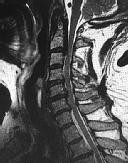

Figures 1 and 2 show sagittal and axial MRI from an 83-year-old woman with an ataxic gait, loss of dexterity, and intermittent loss of bowel and bladder control. The symptoms have been getting progressively worse over the past several weeks.

What disease process is most likely the cause of the patient’s symptoms?

4. Pigmented villonodular synovitis Discussion: B

The patient has a pannus at the C1-2 articulation that is compressing the spinal cord and causing myelopathy symptoms. The development of a pannus at this location has been associated with rheumatoid arthritis. Steinberger and associates showed increased morbidity and mortality when using an anterior approach and the surgery took longer than 4 hours. Chieng and associates showed better outcomes and lower complications rates using a posterior approach.